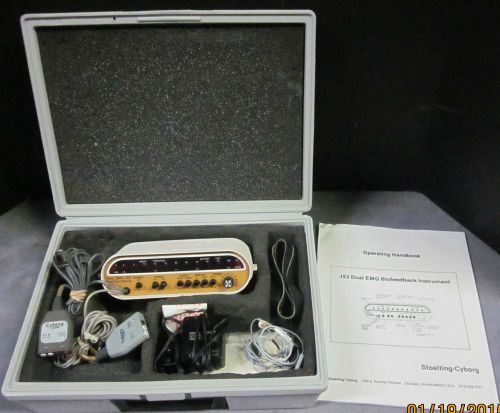

Cyborg J53 Portable EMG - Biofeedback Device